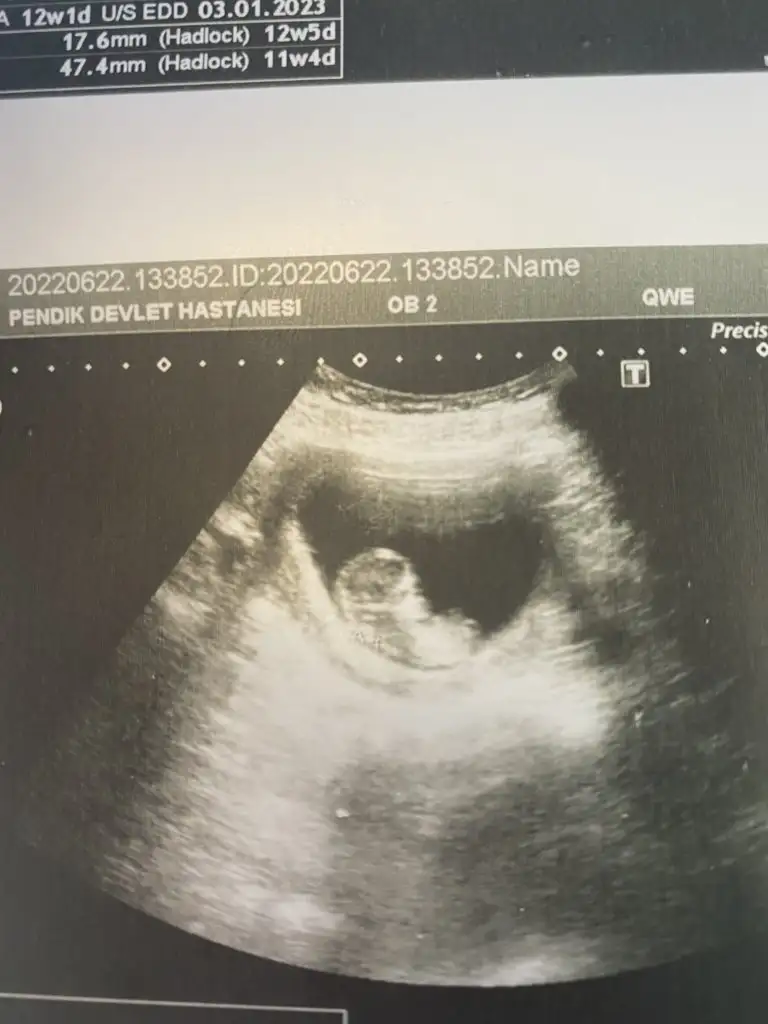

11+3 haftalık gebeyim, karından ultrason görüntüsü bana da tahminde bulunur musunuz :) Ikra meyra Ikra meyra

• 326DE30D-6532-440C-BA94-A531169576F6.webp

326DE30D-6532-440C-BA94-A531169576F6.webp

27,7 KB · Görüntüleme: 42